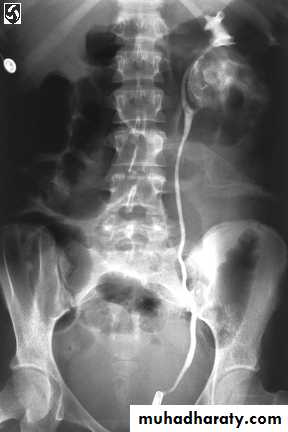

Retrograde pyelography:

Left renal abscess